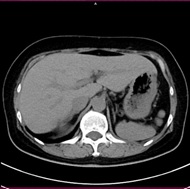

CT検査には、そのまま検査台に寝ていただき撮影する単純CTと造影剤を用いた造影CT検査があります。基本的には単純CT検査を行った後、より詳細に観察したい場合や血管などを観察する場合に行います。造影CT検査は肘(ひじ)のあたりに針を刺し血管内(静脈)に造影剤を入れて撮影します。

単純CT画像 造影CT画像 MPR画像